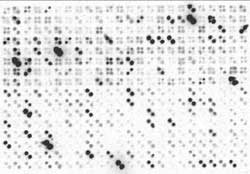

Bildquelle: Philipps-Universität MarburgBeispiel eines Ergebnisses mit dem diagnostischen Biochip. Jedes Gen ist durch zwei Punkte repräsentiert. Die Aktivität eines Gens in einer Tumorprobe führt zu einer Schwärzung der entsprechenden Punkte auf dem Chip. Dieser molekulare Fingerabdruck stammt von einem bösartigen Tumor der Bauchspeicheldrüse.In der Vergangenheit wurden zahlreiche Gene identifiziert, deren Aktivität in verschiedenen Tumorarten der Bauchspeicheldrüse spezifisch herauf- oder herabgesetzt ist. Nur einzelne dieser Gene zu untersuchen, reicht aber für eine exakte Diagnose oftmals nicht aus. Die Wissenschaftler des Forschungsverbundes PaCaNet im Nationalen Genomforschungsnetz NGFN haben sich deshalb entschieden, mit Hilfe eines Biochips parallel, also direkt in einer Untersuchung, die Aktivität von 588 unterschiedlichen Genen zu analysieren. „So erstellen wir einen genetischen Fingerabdruck des Tumors und können mit 92-prozentiger Sicherheit sagen, um welche Art von Tumor es sich handelt und ob der Tumor bösartig ist“, beschreibt Dr. Buchholz. Man spricht hierbei von der Sensitivität des diagnostischen Tests. Die Spezifität des Biochips, also die Genauigkeit, mit der ein Tumor als eindeutig gutartig eingeordnet werden kann, liegt bei 75 Prozent. „Das ist eine Präzision, die mit anderen diagnostischen Methoden bislang nicht erreicht wurde“, fasst Dr. Buchholz zusammen. Die Forschungsarbeiten werden vom Bundesministerium für Bildung und Forschung (BMBF) unterstützt.

„Für unsere Biochip-Analyse benötigen wir nur eine kleine Gewebeprobe des Tumors, eine sogenannte Feinnadel-Biopsie“, sagt Professor Gress. Daraus werden die RNA-Botenmoleküle isoliert, aufbereitet und dann auf den Chip getropft. Dort bindet die RNA an genau die Stelle des Chips, wo das passende Genfragment sitzt. Da die RNA-Moleküle zuvor radioaktiv markiert wurden, erzeugt jede Bindung ein Signal auf dem Chip. Ein Computer wertet diese Signale aus und erstellt dann den „Fingerabdruck des Tumors“, ein Muster aus Punkten, die die Aktivitäten der jeweiligen Gene im Tumor angeben. Denn je aktiver ein Gen ist, desto mehr RNA-Botenmoleküle werden in der Zelle produziert. Und je mehr RNA-Moleküle auf dem Chip binden, umso stärker ist das Signal. Die Gesamtheit der Signale liefert den Forschern dann die nötige Information über den Tumor. „Mit Hilfe unseres 588-Gene-Biochips für das Pankreaskarzinom erhoffen wir uns eine schnellere und präzisere Diagnose als bisher, die dann auch eine bessere Basis für Therapieentscheidungen bieten soll“, folgern die Marburger Forscher.